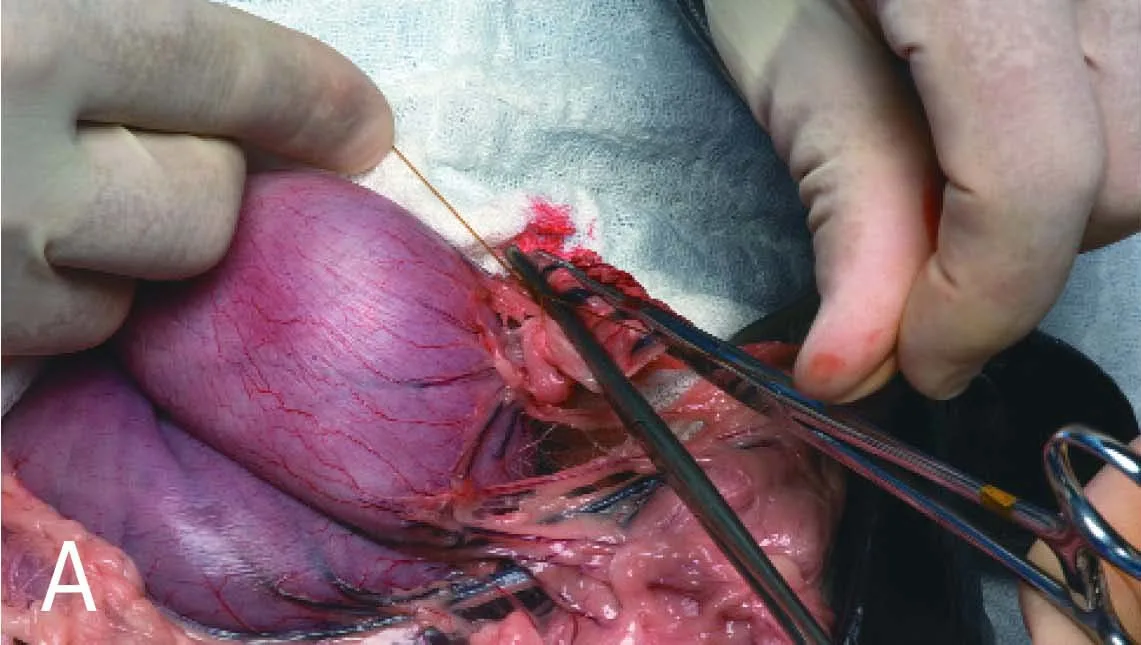

Securely double-ligate the pedicles and remove the forceps. Ligatures are ideally placed several millimeters or more from the cut pedicle edge to allow tissue to "mushroom" and help prevent ligature slippage. In A, a ligature is shown encircling the short gastric artery pedicle just below forceps #1. Notice the deformed "spread out" pedicle that will not allow a tight ligature to be formed if the forceps is not released. In B, the pedicle is constricted after the forceps is removed and the ligature tightened within the previously crushed area.